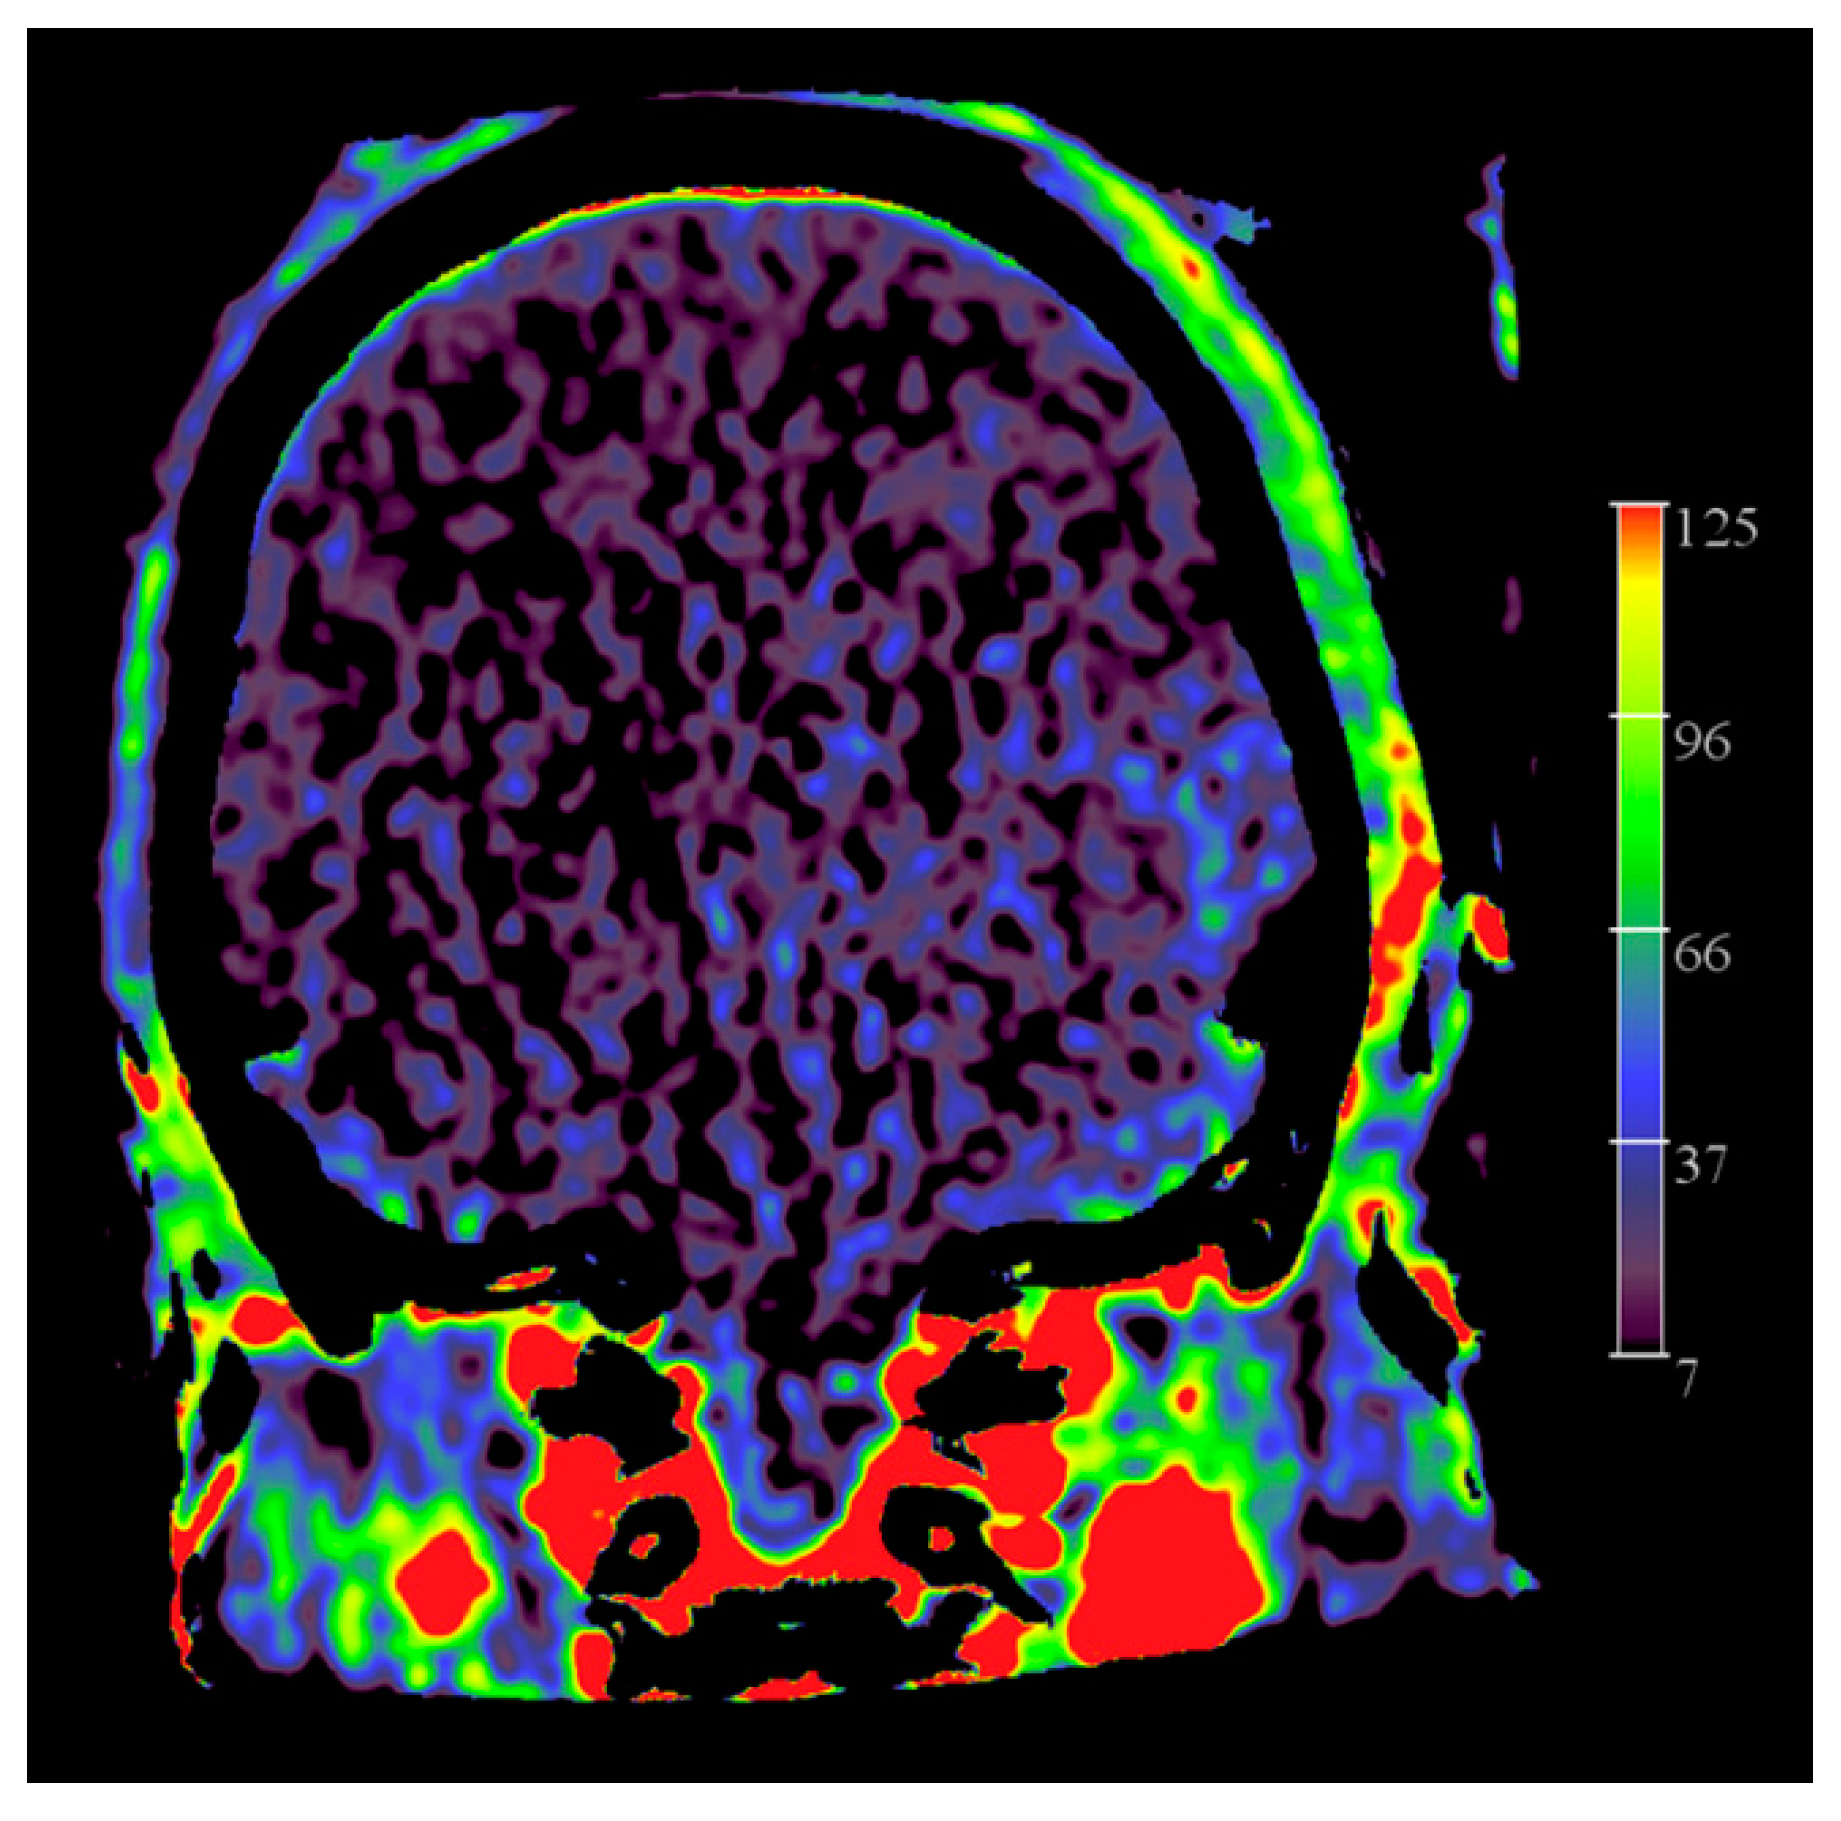

Figure 10 represents FD CT PBV mapping of a brain-dead patient.

Figure 10.

FD CT PBV imaging in a patient with no intracranial flow. Coronal PBV MIP reformation demonstrates filling of the ECA vascular territories, including middle meningeal artery, but no filling of pial arteries.